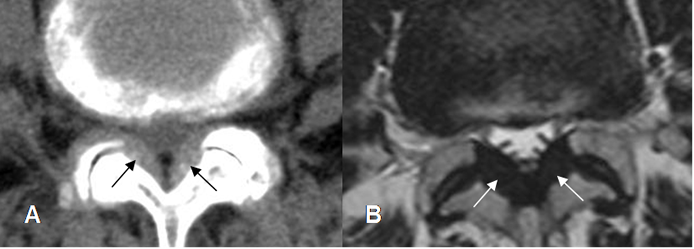

Fig 64. Canal estrecho lateral.

A: TAC axial en ventana de tejido y B: TAC axial en ventana de hueso. Estenosis del receso lateral, por hipertrofia de articulaciones intervertebrales y presencia de osteofito. (Flecha gruesa). Disminución de la grasa que rodea la raíz nerviosa. (Flecha delgada).